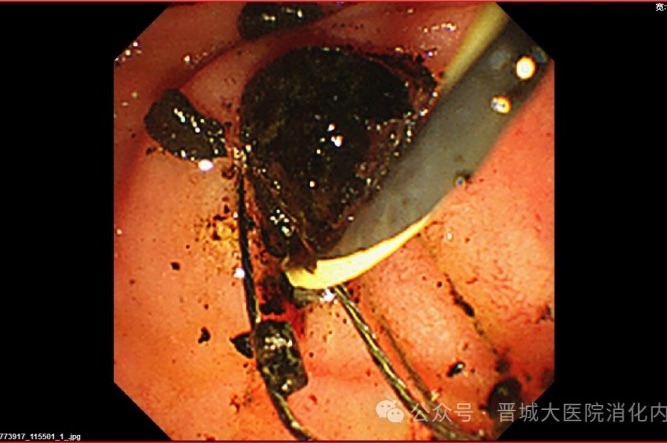

手術(shù)中,普通外科首先為李阿姨行“腹腔鏡膽囊切除”(LC),消化內(nèi)科團(tuán)隊(duì)緊隨其后行ERCP,造影發(fā)現(xiàn)膽總管內(nèi)有多個(gè)巨大結(jié)石,最大約2.5×2.1厘米,且結(jié)石堅(jiān)硬,形如煤渣樣,使用取碎石一體網(wǎng)籃多次反復(fù)碎石、取石。用生理鹽水反復(fù)沖洗膽道,無結(jié)石殘留。利用微創(chuàng)技術(shù)順利完成膽囊切除及膽總管結(jié)石取石,手術(shù)時(shí)間短、創(chuàng)傷小、恢復(fù)快。